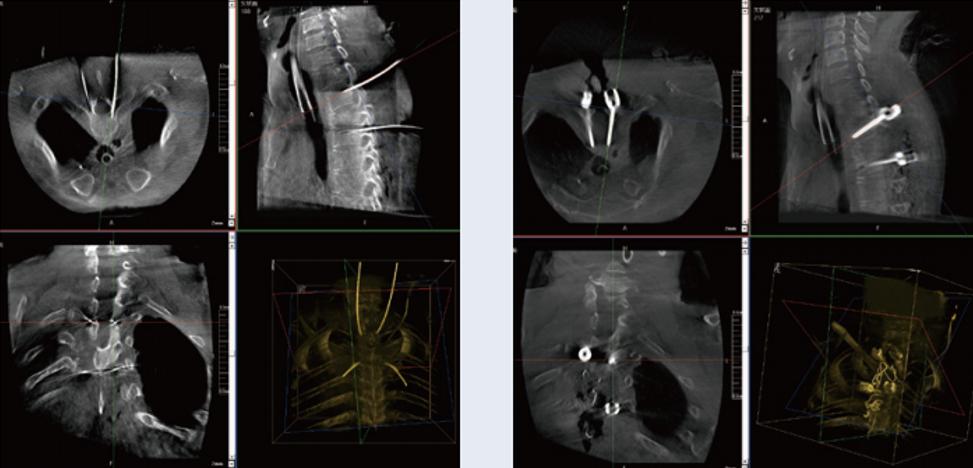

螺釘規劃后的圖像

植入螺釘后的圖像

術中三維C形臂與脊柱導航機器人配合應用,實現準確定位,確保了手術安全、高效完成。術后二維、三維影像顯示手術效果良好,達到預期目的。